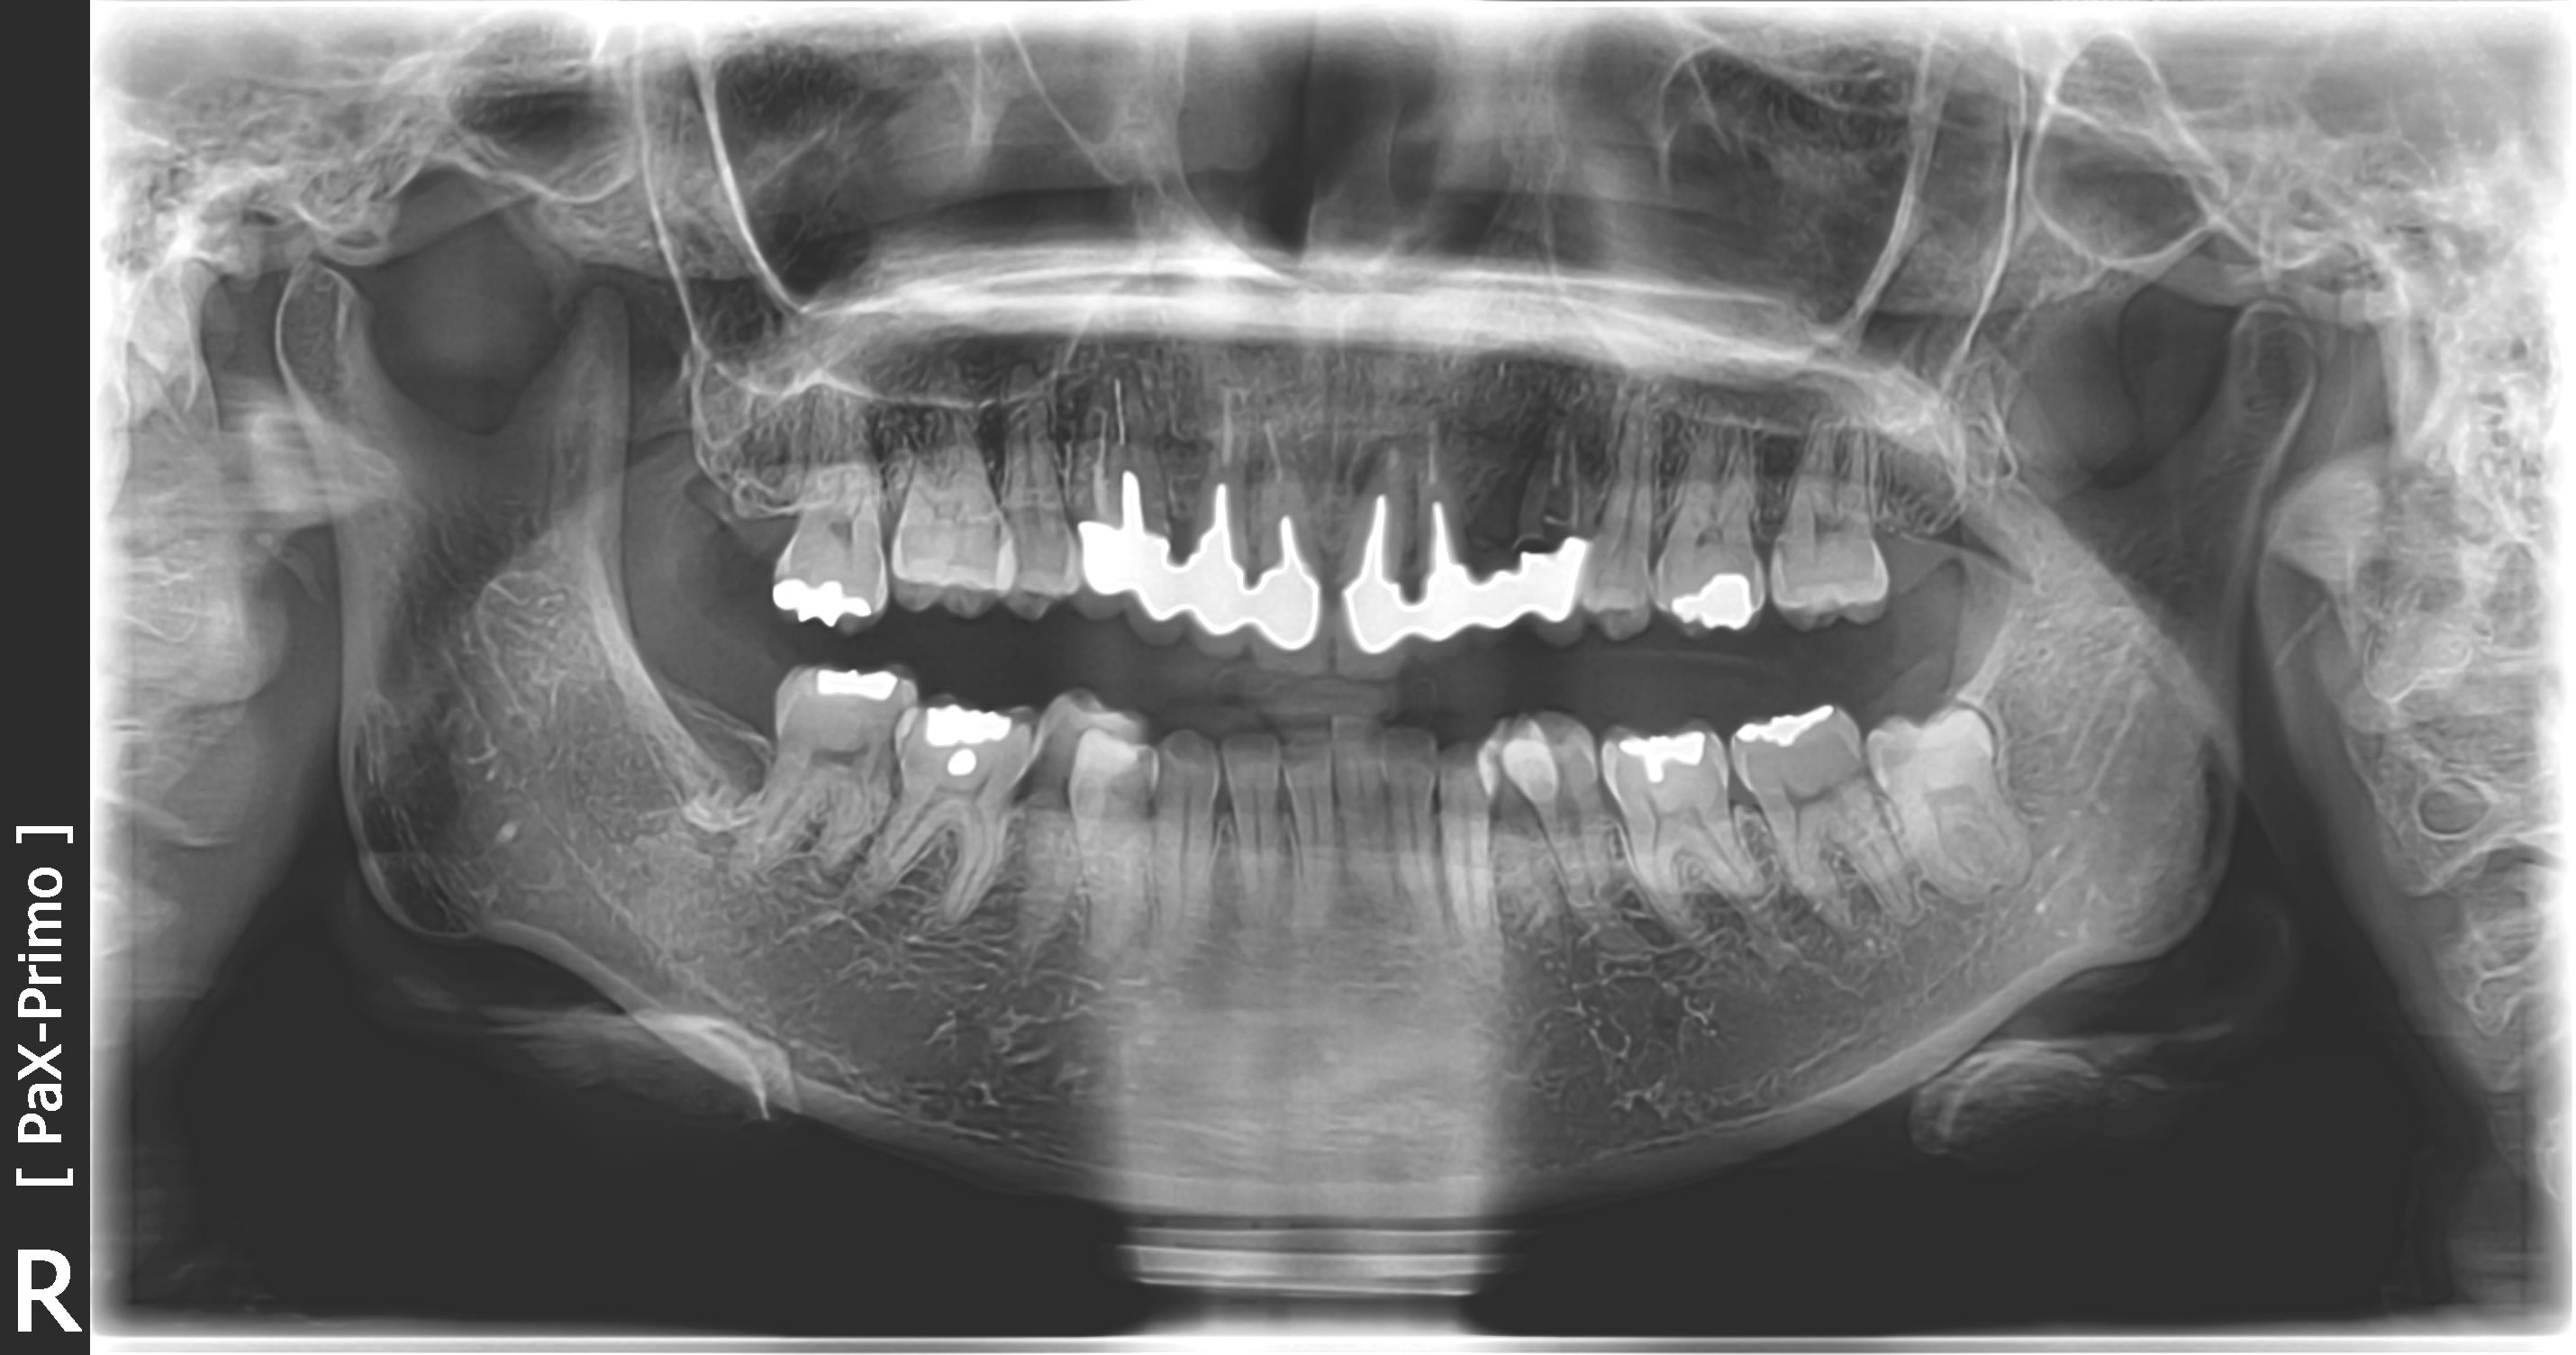

Ensuite vue la perte osseuse sur 24 en mesial c'est pas evident...

J'imagine que l'ideal c'est 3 implants et bridge dessus non? avec le risque esthetique niveau ligne des collets entre 11-21 qui s'en suivra.

A mon avis sa dvo est bonne comme chaque fois , c est le plan d occlusion qui ne va pas .

On ne voit pas le bord libre des incisives du bas , c est dommage pcq c est le bord libre des incisives du bas qui sont le depart de toute reflexion avant grande reconstruction .

au depart la 23 devait etre tres vestibulée ( si elle etait sur l arcade ) et les centrales en papillon avec chevauchement .

tout le secteur ant 20 a été rentré de meme que la courbure générale .

à tout les coups elle ferme avec un préférence par le coté droit avec un sur guidage en verrouillage ( en fin de mouvement ) sur le secteur 20 . il est donc interférant .

à cela tu rajoutes un sur contact cingulaire prothetique sur les centrales + sur 22et 23 .

je dis ça pcqu il y a des ic et que dans les cas de recouvrement , ç est tres tres rare qu il y ait la place de passer des ic + armature de bridge .

ce bridge a été fait pour des raisons esthétiques et ne doit pas être vieux .

-les fractures ceram peuvent aussi resulter de la mobilité du bridge, du fait de l'explosion radiculaire sous jacente, l'axe erroné sur 21 peut aussi participer à une instabilité de la construction.

- si la DVO est bonne (Enlaye plus haut) l'augmenter pour avoir un espace utile à la prothèse ne peut se faire qu'à la marge pour rester pfysiologiquement et esthetiquement acceptable.... ce n'est pas resolutif.

- les courbes occlusales favorisent la plongée pre maxillaire, oui , la solution remonte à la source : comment contrer ce paramètre ? et un alignement des collets alors qu'ilfaut s'attendre à une perte tissulaire post extractionnelle importante.... On ne sait ni si elle decouvre dans le sourire, ni le tonus labial (levres minces non adaptables à une nouvelle ligne de sourire), ni sa phonétique.